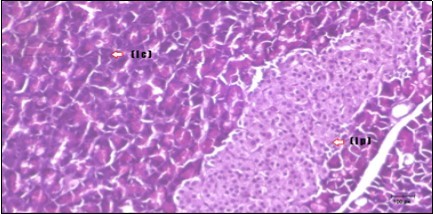

Pancreas Histopathological Observations

Histological examination of pancreas of the control rats showed normal sized islets of pancreas (Ip) compared to the diabetic rats which showed markedly atrophic islets of pancreas (I.p.) (Figure 8 and Figure 9). Pancreas of in groups (3) and (4) rats showed mild atrophic islets of pancreas (I.p.) with inflammatory cellular infiltrate (Figure 10 and Figure 11). The pancreas of rats in group (5) showed nearly normal islets of pancreas (I.p.) with few inflammatory cellular infiltrate (I.c.) (Figure 12).

Figure 9.Photomicrogragh of pancreas section of diabetic rat showing the markedly atrophic islets of Langerhans. (arrow) (H&E) (40X).

Figure 10.Photomicrogragh of pancreas section of treated rat with Fenugreek showing less improved islets of Langerhans with more cells (star). (H&E) (40X).

Figure 11.Photomicrogragh of pancreas section of treated rat with Glimepiride showing mildly improved of isled of Langerhans with large number of cells (dashed-arrow). (H&E) (40X).

Figure 12.Photomicrogragh of pancreas section of treated rat with both Fenugreek and Glimepiride showing nearly normal islets of Langerhans with spindle (arrow) & polygonal cells (dashed- arrow). (H&E) (40x).

Histopathological observation in diabetic control showed degenerative changes in both endocrine and exocrine pancreases. A probable explanation may be related to oxidative stress resulting from hyperglycemia which decreases the antioxidants levels and increases ROS 33 and the activities of antioxidant enzyme were altered in diabetic rats. These effects further exacerbate the development and progression of diabetes complications and these may represent the causes of degeneration revealed in histological sections. Fenugreek improved blood glucose levels and insulin, lowered pancreatic islet and β-cells damage which may be attributed to its immune modulatory activity and insulin stimulation action along with its antioxidant potential 32. Glimepiride caused restoration of morphology of beta cell of diabetic and it increased percentage of beta cells 34. This protective effect could be attributed to the antioxidant properties of Glimepiride. Combination therapy improves the protective effect of both therapies alone.